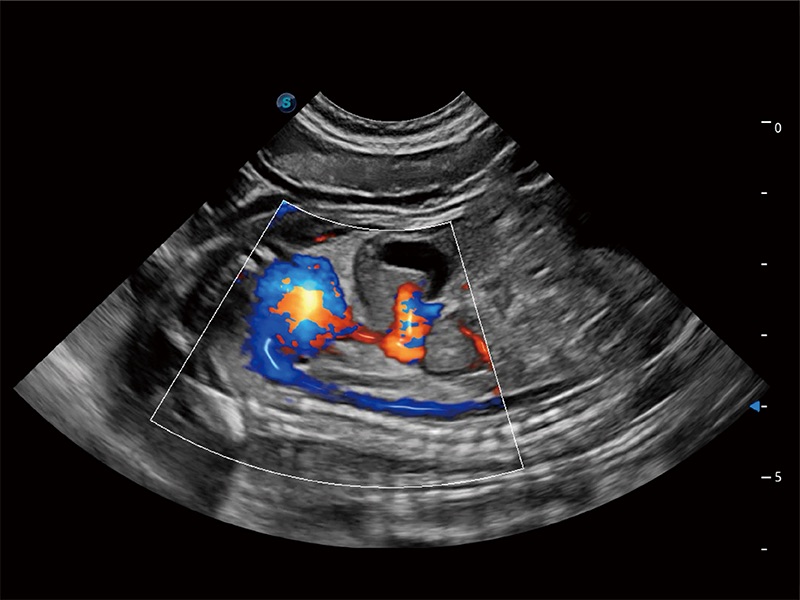

• Bright Flow 立體血流成像

在傳統(tǒng)二維血流成像的基礎(chǔ)上,呈現(xiàn)血流的立體感,具有動感的生命力之美。即便是微小的血管也能輕松應(yīng)對,提高了血流的視覺敏感性。

(犬)胎兒主動脈弓立體血流

(犬)胎兒四腔心